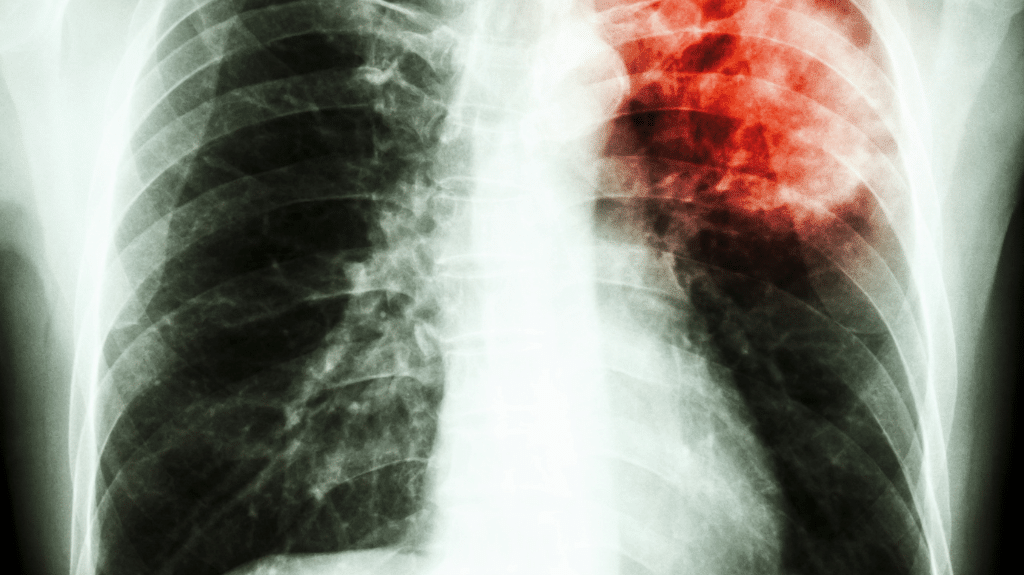

Journée mondiale contre la tuberculose : la Tunisie enregistre 26 nouveaux cas pour 100 000 habitants chaque année

26 nouveaux cas pour 100 000 habitants

Le chef du service des maladies pulmonaires à l’hôpital Hedi Chaker de Sfax, le Dr Sami Kamoun, a révélé que la Tunisie enregistre chaque année 26 nouveaux cas de tuberculose pour 100 000 habitants, soit environ 3 500 cas annuels. Il a tenu à rappeler que l’État tunisien assure la gratuité totale du traitement pour tous les patients atteints de cette maladie.